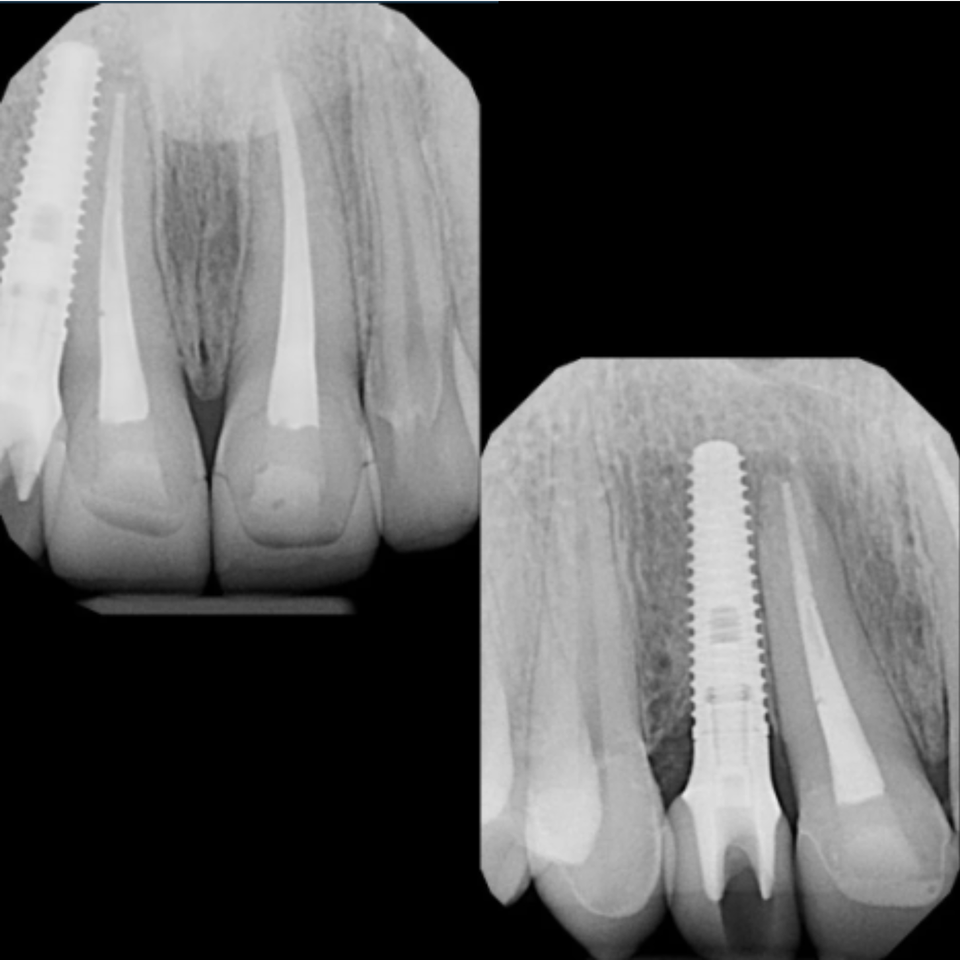

At Elite Dental Group, we provided emergency care that included root canal treatment on the upper central incisors. Dr. Satish Palayam performed an immediate implant placement for the right lateral incisor and completed a crown lengthening procedure on the palatal side of the right central incisor to support proper restoration. A provisional bridge was then placed to maintain both function and esthetics throughout the healing phase.

After a four month healing period, the final crowns were placed on the central incisors, and the implant for the right lateral incisor was successfully restored and finalized.